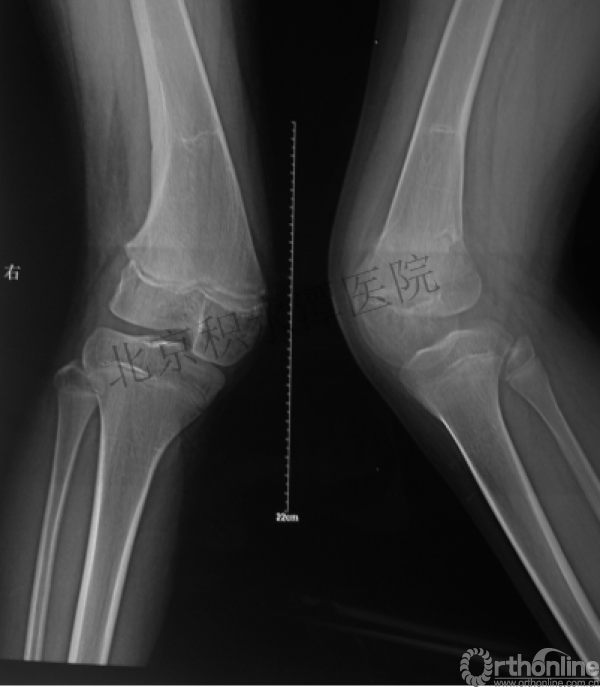

病例分享六

7岁、男孩,桡骨远端骨折

原始损伤片

手法整复后 - 45分钟!

伤后4天复查

伤后30天!

医生的处理方法!——医生终于没有坚持自己的原则!

伤后40天—切开复位内固定!

伤后18个月

如何面对?

心情之压抑无以言表!

手术历时近 5小时!心情之压抑无以言表!因为当时的经治医生是他们的进修生!感觉是他们的失职甚至渎职!

唯一可以肯定—预后不佳!郭教授是党员!是无神论者!但是很诡异的事情:手术中发生—C形臂看不清!拍片条件总是调节不好!手术器械换了三套!内固定钢板总不合适!

术后15月,虽然家长满意了,但是他们医生不满意!